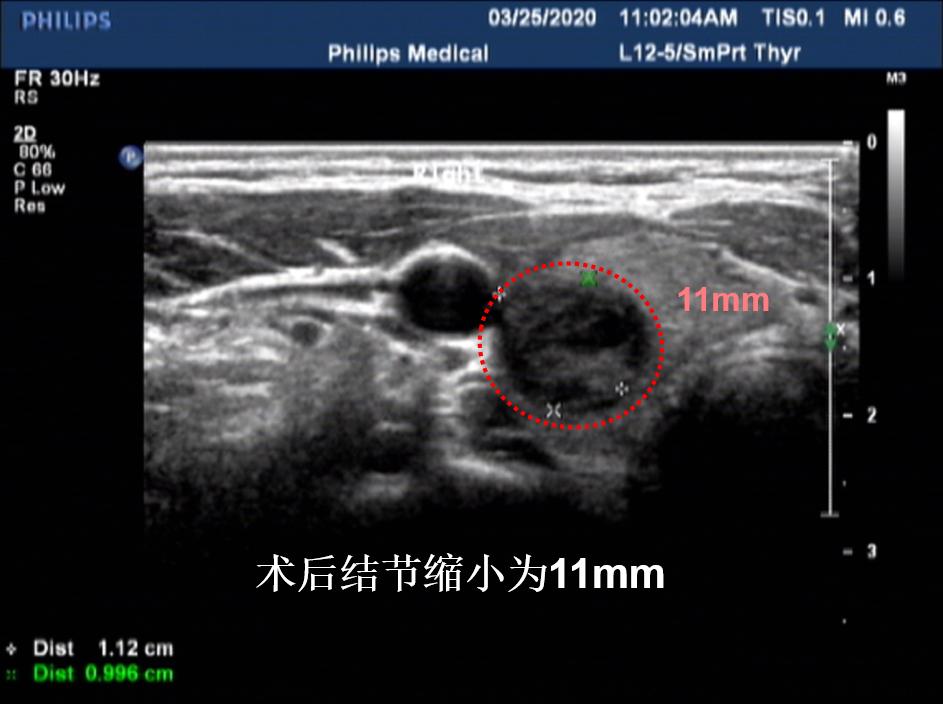

病例①:甲状腺右叶3cm结节消融前后对照,术后体表已触及不到肿物

微创消融前后超声对比,体积缩小93%